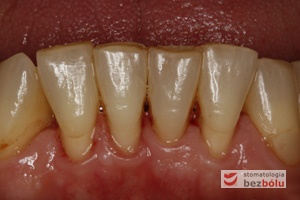

Status dolnego łuku zębowego - mierny stopień zaniku dziąsła- nieliczne wypełnienia przyszyjkowe i okluzyjne

Status dolnego łuku zębowego – mierny stopień zaniku dziąsła- nieliczne wypełnienia przyszyjkowe i okluzyjne